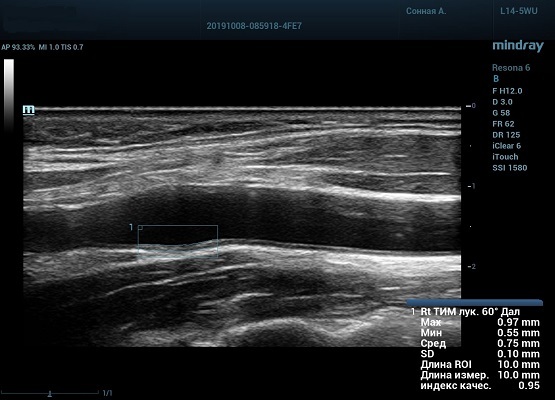

Auto IMT (автоматическое определение толщины комплекса интима-медиа)

Автоматическое измерение толщины передней и задней стенки, предоставляющее точную информацию о состоянии сонной артерии.